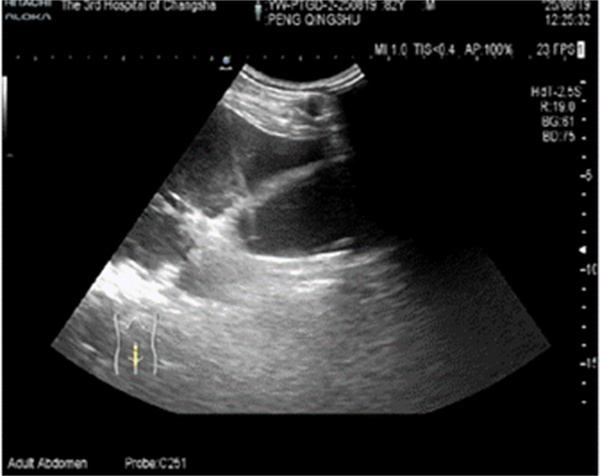

穿刺造瘘术中超声

入院紧急评估及权衡后,医护团队决定行超声引导下经皮肝胆囊穿刺造瘘术引流出脓性胆汁,为老人缓解症状。可好景不长,穿刺几天后由于胆汁浓稠、胆泥形成导致引流管不通畅,彭爹爹再次出现发热及右上腹疼痛,引流量减少的情况。